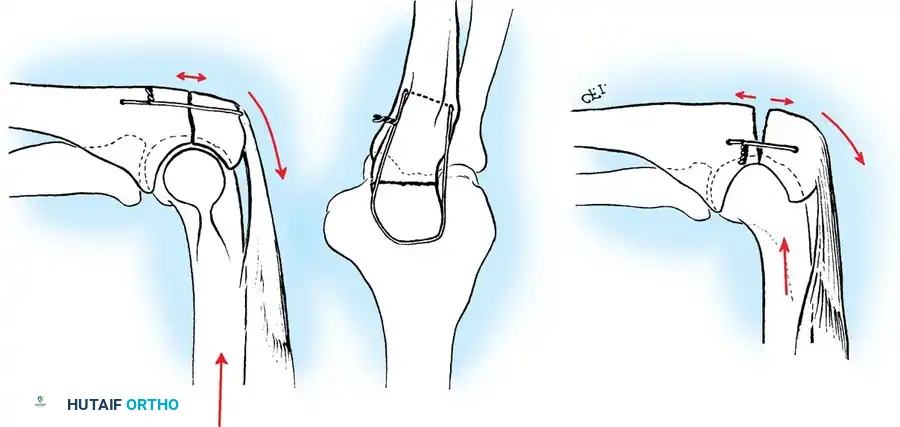

Biomechanics of the Tension Band:

The superficial (posterior) surface of the olecranon is the tension side of the bone. A figure-of-eight wire placed on this surface converts the tensile forces generated by the triceps into compressive forces across the articular fracture line, utilizing the humeral trochlea as a fulcrum.

Surgical Warning: A simple wire loop is biomechanically inferior to a figure-of-eight loop. If a simple loop is used—especially if its axis lies anterior to the mid-axis of the olecranon—the pull of the triceps will cause the fragments to separate posteriorly, leading to articular step-off and limited extension.

Fig. 54-53 A and B, Simple loop is not as satisfactory as figure-of-eight loop for fixing fracture of olecranon. C, Simple loop is insufficient when its long axis is in or anterior to long axis of olecranon.

Fig. 54-54 Internal fixation of olecranon with tension band wire loop. Wire passed through hole drilled in distal fragment and through triceps aponeurosis adjacent to bone. Figure-of-eight loop adds stability to fracture and prevents distraction and posterior bowing.

2. Intramedullary Fixation with Tension Band

If the fracture is more distal, or if there is a tendency for the proximal fragment to angulate posteriorly, a simple tension band wire is insufficiently stable. In these cases, intramedullary fixation (using Kirschner wires or a large cancellous screw) is combined with the tension band.

Kirschner Wires vs. Cancellous Screws:

* K-wires: The AO technique utilizes two parallel K-wires (1.6 mm or 2.0 mm) driven down the medullary canal. To prevent proximal migration, the K-wires must engage the anterior cortex of the ulna distal to the coronoid.

* Cancellous Screw: A biomechanical analysis by Murphy et al. demonstrated that a long 6.5-mm or 7.3-mm AO cancellous screw combined with a figure-of-eight wire provides a significantly stronger construct than K-wires. The screw must be long enough to achieve secure purchase in the ulnar diaphysis.

Fig. 54-55 Olecranon fracture repaired with long 6.5-mm AO cancellous screw and figure-of-eight tension band wire loop. Screw must engage cortex of diaphysis of ulna.